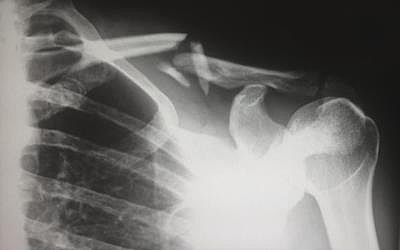

Die schwere Körperverletzung tritt nach der Tat ein. Sie orientiert sich an den Folgeschäden des Opfers. Beispielsweise wenn eine langanhaltende psychische Krankheit auftritt oder jemand das Gehör durch einen lauten Knall verliert.

Bei schwerer Körperverletzung nach § 226 StGB erhält das Opfer in den meisten Fällen Anspruch auf Schmerzensgeld . Eine schwere Körperverletzung liegt vor, wenn:

[…] die verletzte Person 1. Das Sehvermögen auf einem Auge oder beiden Augen, das Gehör, das Sprechvermögen oder die Fortpflanzungsfähigkeit verliert, 2. Ein wichtiges Glied des Körpers verliert oder dauernd nicht mehr gebrauchen kann oder 3. In erheblicher Weise dauernd entstellt wird oder in Siechtum, Lähmung oder geistige Krankheit oder Behinderung verfällt […]

§ 226 StGB Die Freiheitsstrafe hierfür beträgt ein Jahr bis zehn Jahre. Wurde die Person absichtlich verletzt, liegt die Freiheitsstrafe nicht unter drei Jahren.